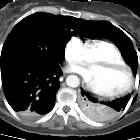

traumatic pericardial rupture